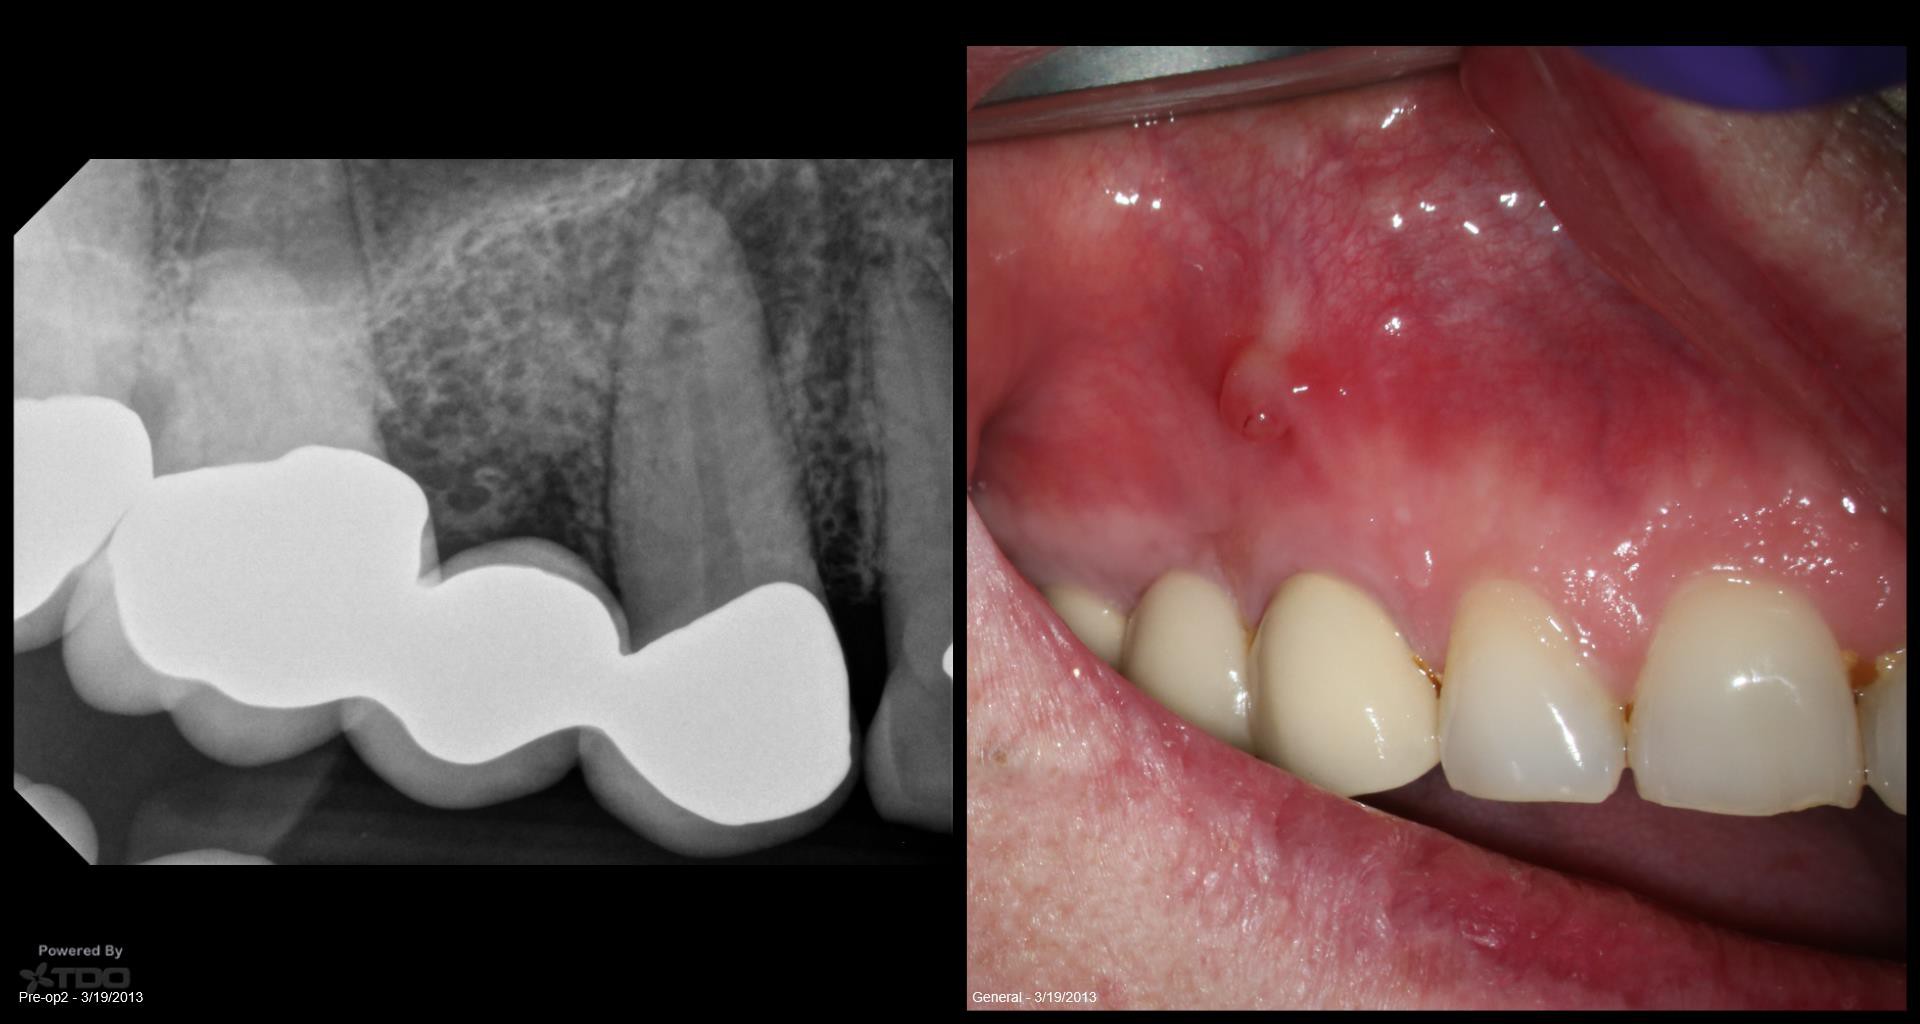

5 yr CBCT recall

Entire buccal plate missing. CBCT at 5 years suggests most, but not all, bone has regenerated. As canine bridge abutment, it is subjected to some occlusal trauma. gbc